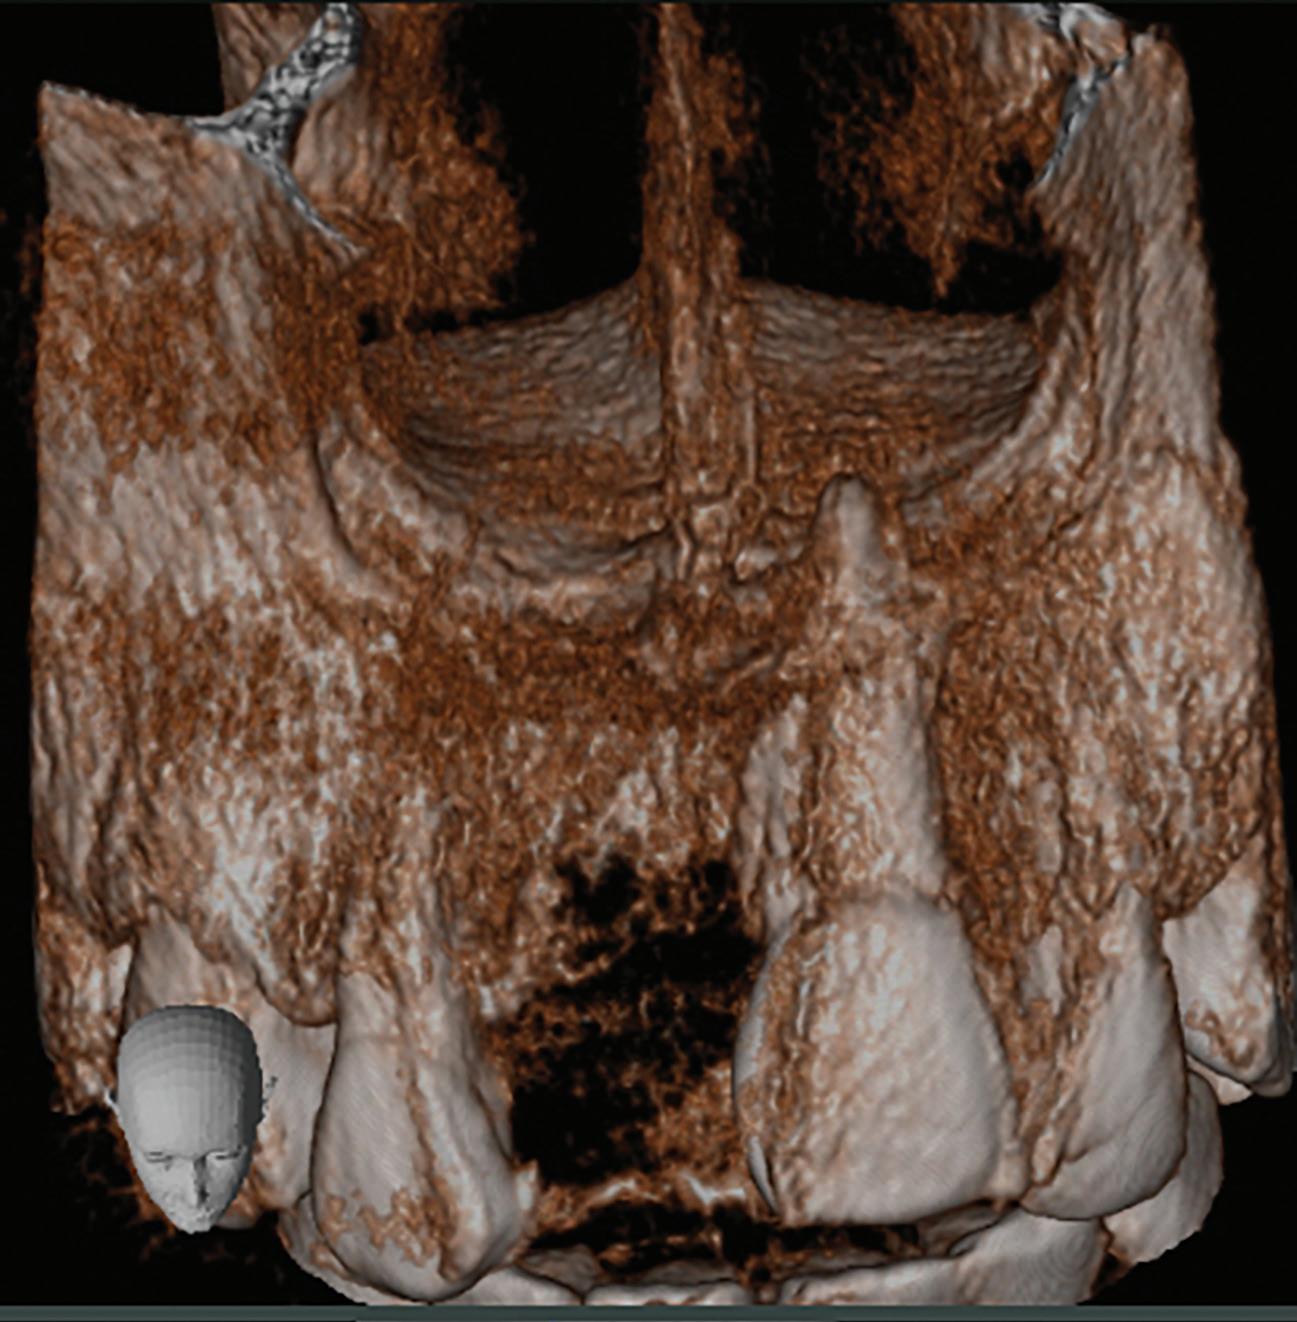

These CAIPP lesions are best identified and monitored with high-resolution CBCT scans (Fig 5). However, even advanced CBCT systems, with voxel sizes as small as 0.075 mm, are not capable of reliably detecting cracks, which are typically much narrower.45 Therefore, the presence of a CAIPP defect, combined with careful clinical diagnostics and evaluation, remains the most reliable indirect indicator of a crack with radicular extension.

The presumed clinical significance of a lingering CAIPP defect is that the persistent biofilm in the crack can lead to further periodontal breakdown and symptoms. However, the changes in these areas were monitored over the course of

previous studies, and these bony lesions did not progress over time and remained asymptomatic.4,26 Together, these studies demonstrated that the persistent bony defect adjacent to the cracks may remain stable and asymptomatic over time, making saving teeth with this technique a realistic option for patients.

Fig 5. CBCT images of a crack-associated isolated periodontal pocketing defect associated with a distal crack in the mandibular right first molar. A. Sagittal view showing angular crestal bone loss (arrow) along a distal radicular crack at the cervical margin. B. CBCT 3-dimensional rendering showing the defect (arrow) at the distal root. C. Axial view showing the defect (arrow) at the distal root.